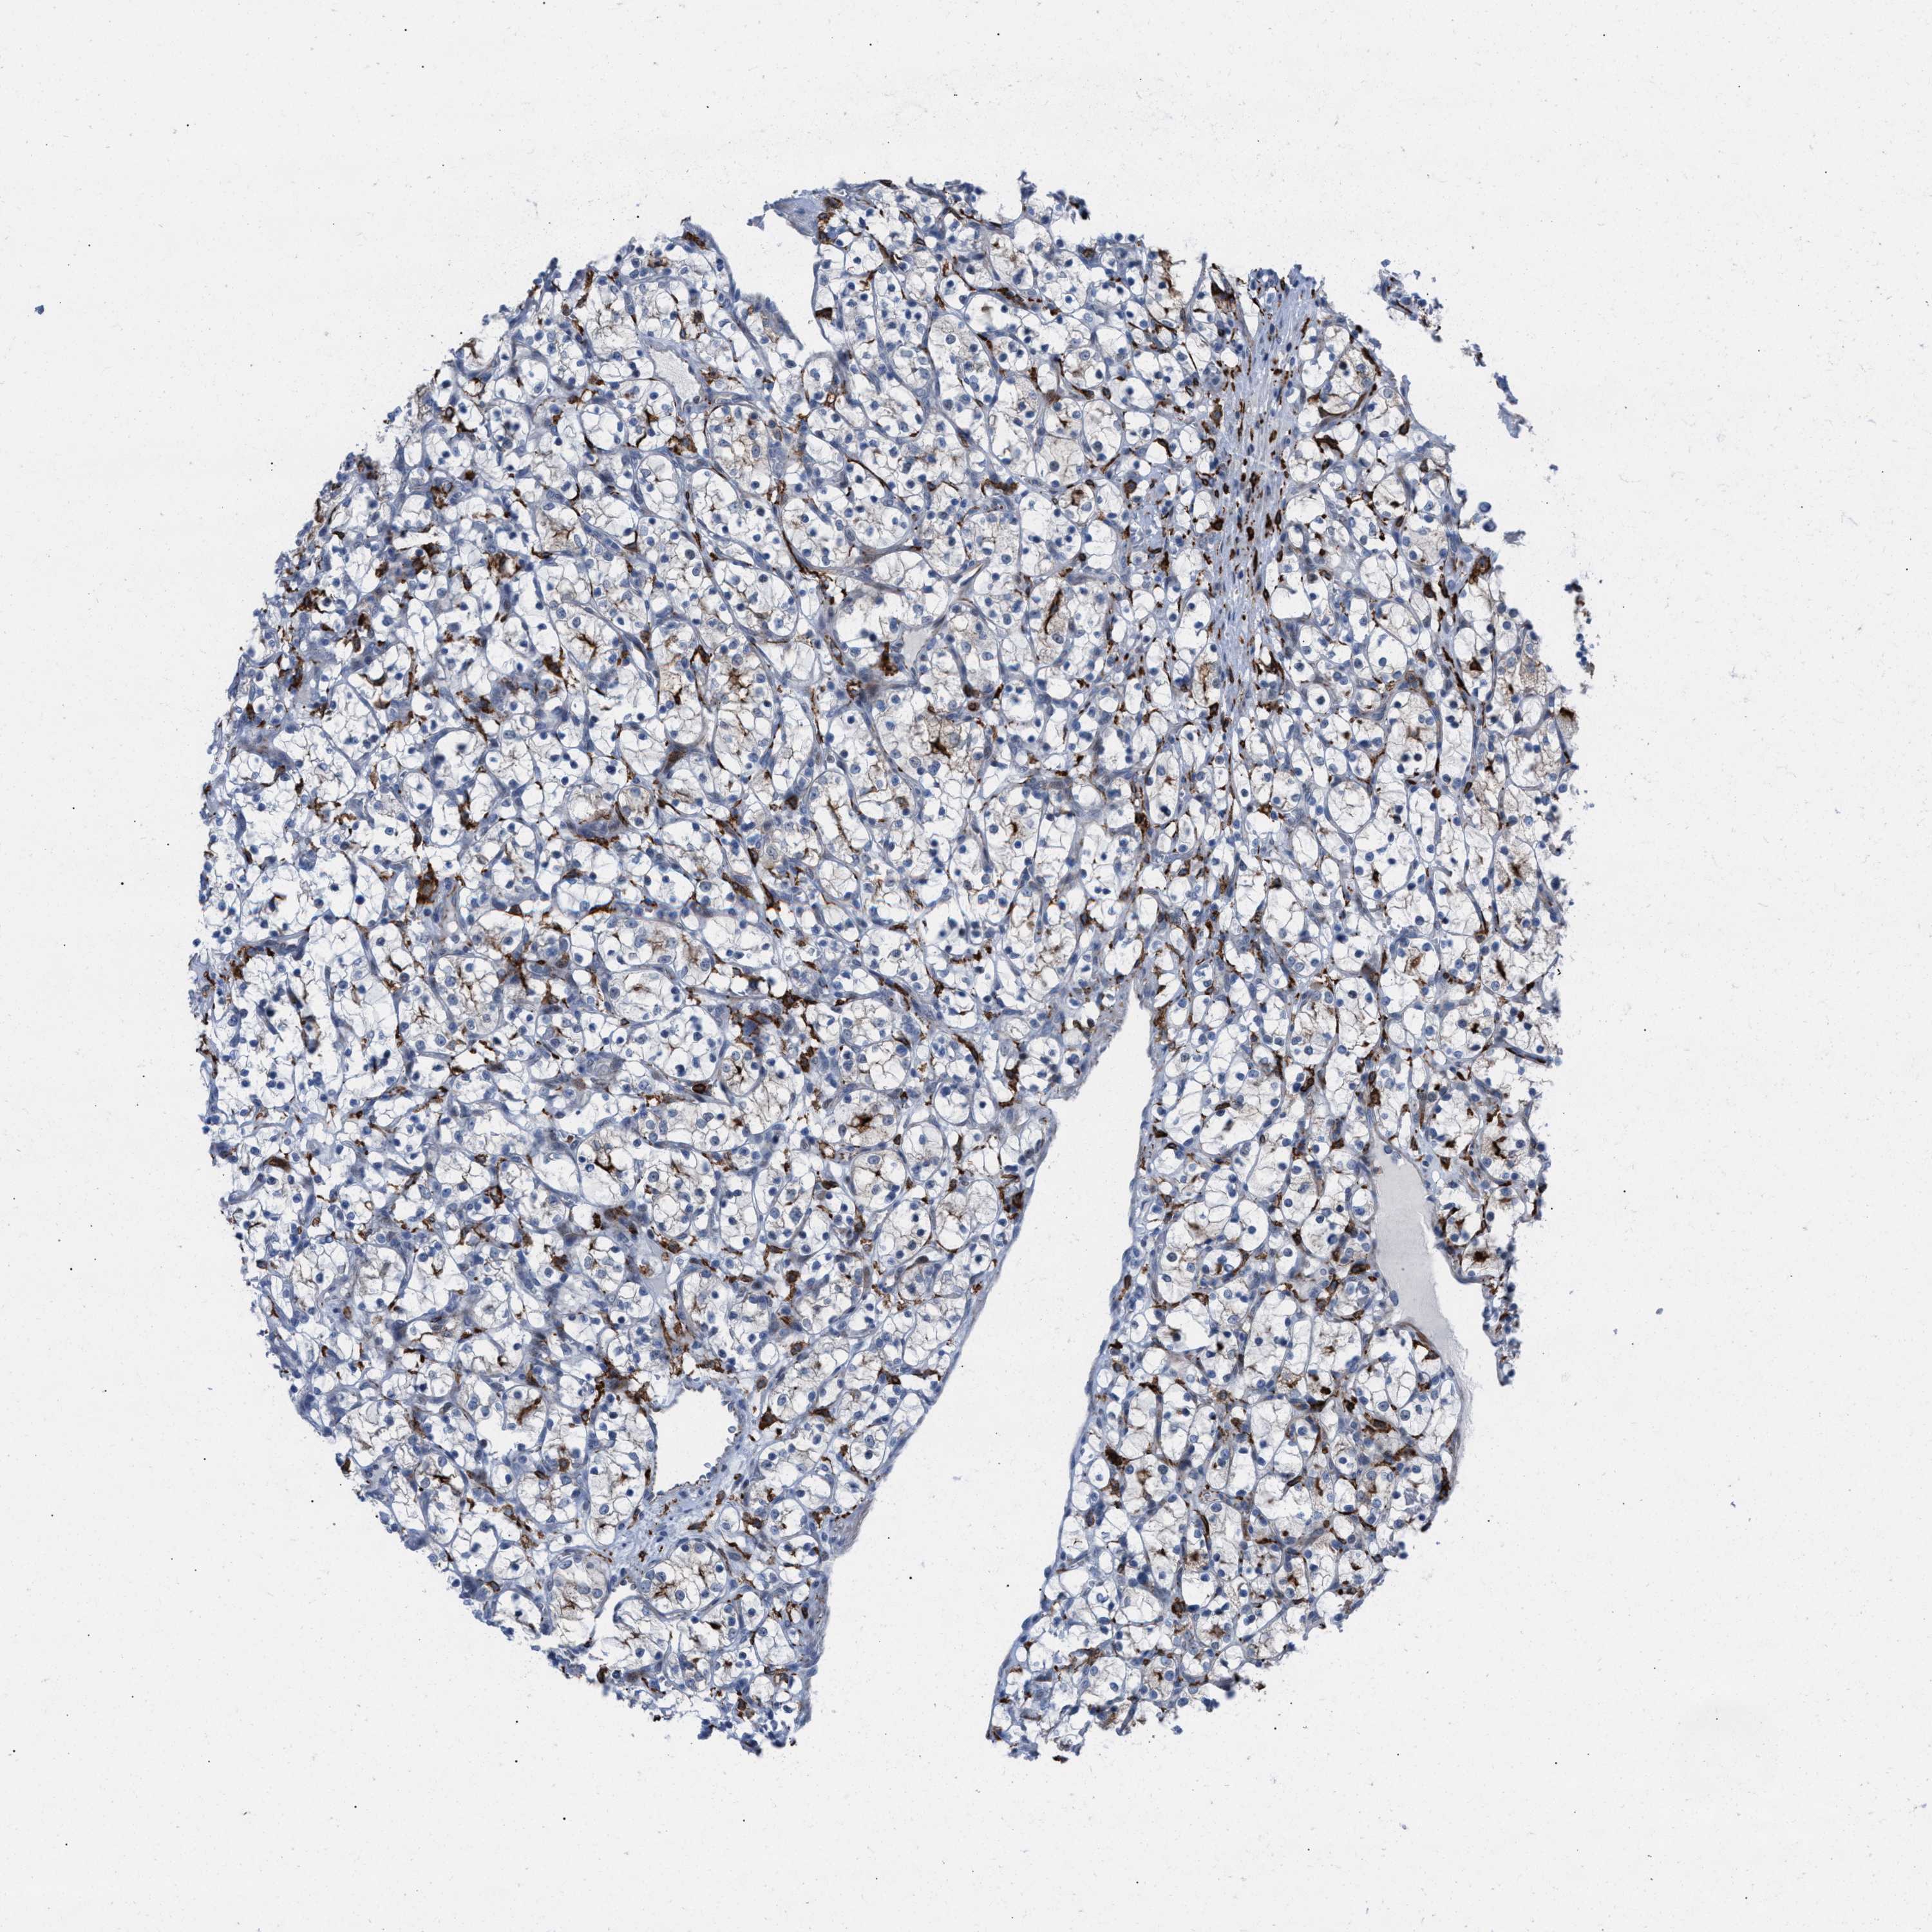

KIDNEY RENAL CLEAR CELL CARCINOMA (TCGA) - Interactive survival scatter ploti

The Survival Scatter plot shows the clinical status (i.e. dead or alive) for all individuals in the patient cohort, based on the same data that underlies the corresponding Kaplan-Meier plots. Patients that are alive at last time for follow-up are shown in blue and patients who have died during the study are shown in red.

The x-axis shows the expression levels (FPKM) of the investigated gene in the tumor tissue at the time of diagnosis. The y-axis shows the follow-up time after diagnosis (years). Both axes are complimented with kernel density curves demonstrating the data density over the axes. The top density plot shows the expression levels (FPKM) distribution among dead (red) and alive patients (blue). The right density plot shows the data density of the survived years of dead patients with high and low expression levels respectively, stratified using the cutoff indicated by the vertical dashed line through the Survival Scatter plot. This cutoff is automatically defined based on the FPKM cutoff that minimizes the p-score. The cutoff can be changed by dragging the vertical line or by entering a cutoff value in the square labeled "Current cut-off".

Under the Survival Scatter plot the p-score landscape (black curve; left axis) is shown together with dead median separation (red curve; right axis). Dead median separation is the difference in median mRNA expression between patients who have died with high and low expression, respectively. It is calculated as follows: median FPKM expression of dead patients with high expression - median FPKM expression of dead patients with low expression. This is intended to aid the user in visually exploring custom cutoffs and the associated p-scores and dead median separation.

Individual patient data is displayed and can be filtered by clicking on one or more of the category buttons on the top of the page. Categories describing expression level and patient information include: high, low, alive, dead, female, male and tumor stages. The scale of the x-axis can be toggled between linear and log-scale by clicking on the "x log" button. Mouse-over function shows TCGA ID, patient information and mRNA expression (FPKM) for each patient.

& Survival analysisi

Kaplan-Meier plots summarize results from analysis of correlation between mRNA expression level and patient survival. Patients were divided based on level of expression into one of the two groups "low" (under cut off) or "high" (over cut off). X-axis shows time for survival (years) and y-axis shows the probability of survival, where 1.0 corresponds to 100 percent.

SLC47A1 is validated prognostic, high expression is favorable in Kidney Renal Clear Cell Carcinoma (TCGA)

: 143.53

Average pTPM 114.2

Number of samples 521